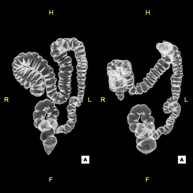

La colonoscòpia virtual és una tècnica no invasiva que permet la visualització tridimensional i bidimensional de l'intestí gros o del còlon mitjançant la presa seqüencial d'imatges captades amb TC Multidetector d'última generació. La qualitat de les imatges permet la navegació virtual per l'interior del recte i del còlon gràcies al processament en estacions de treball especialitzades. La preparació de la prova consisteix en realitzar una dieta baixa en fibra tres dies abans de la prova (per netejar el còlon i el recte) i de la ingesta de contrast oral iodat el dia abans de la prova (per marcar les femtes i poder distingir-les correctament de les possibles lesions colòniques). A diferència de la fibrocolonoscòpia, no requereix sedació ni solucions evacuants. La prova es realitza a la sala del TC, on, a través d'un petit tub flexible, s'insufla aire per distendre el còlon. - PAAF (Punció) Abdominal guiada per TC